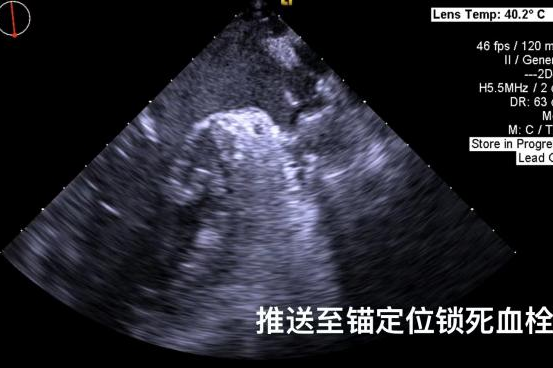

▲半发展固定伞,推送至锚定位锁死血栓

6.png        7.png

其中首场公开演示的左心耳血栓封堵病例拥有极高难度,患者术前TEE显示左心耳血栓形成伴机化,血栓位于心耳中段,近中端絮状物显著 。封堵机遇只有一次,选型和操作稍有失误,城市增长手术风险 。因而手术采取全麻,并装置了抗栓塞脑动脉;ぷ爸,以削减术中风险 。通过TEE疏导下丈量左心耳大幼以及确认左心耳血栓地位,李岳春教授凭借自身丰硕经验最终决定使用LAmbre 2632型号,选取推送式植入法将左心耳血栓牢牢锁死于远端,并且封堵器一次成型,封堵成效极佳,实现后取出脑;ぷ爸,均未见血栓,顺利实现了此台高难度的手术,获得了学员们的一致认可 。